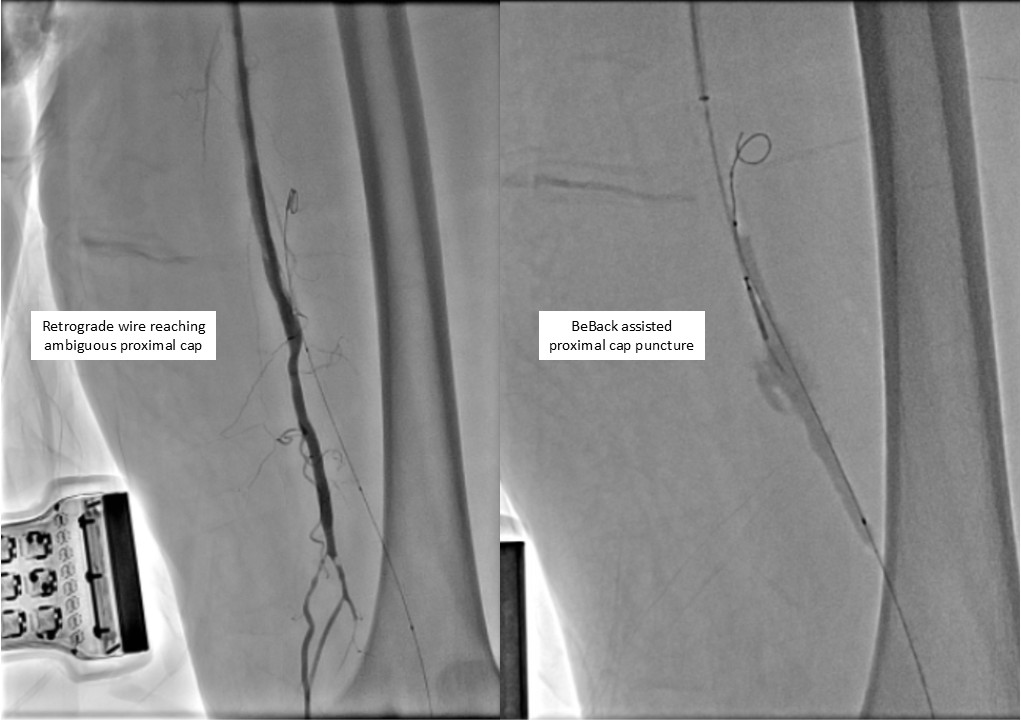

Antegrade puncture was performed, and a microcatheter with a Command 14 guidewire (Abbott Vascular, Santa Clara, CA, USA) was advanced toward the distal SFA but failed to cross because the proximal cap was misidentified due to its blunt and ambiguous appearance. The wire entered aside branch that ran parallel to the true SFA–popliteal course. Given the long chronic total occlusion (CTO) segment and uncertain vessel path, a retrograde approach was pursued to overcome this anatomical ambiguity. Distal ATA access was gained and a CXI Support Catheter (Cook Medical, Bloomington, IN, USA) with a V-18 Guidewire (Boston Scientific, Marlborough, MA, USA) was advanced retrogradely into the popliteal artery but failed to meet the antegrade wire. Another retrograde access from popliteal artery followed a consistent tract. Further attempt from the ATA successfully approached the proximal cap. A 4.0 ¡¿80 mm balloon was advanced retrogradely and inflated at 10 atm. From the antegrade route, the BeBack Crossing Catheter (Bentley InnoMed, Hechingen, Germany) was aimed toward the inflated balloon and successfully punctured the proximal cap, entering the balloon and confirming re-entry. Lesion preparation was completed antegradely, followed by drug-eluting stent deployment in the SFA, drug-coated balloon angioplasty of the popliteal–proximal ATA segment, and plain old balloon angioplasty of the distal ATA to DPA. Final angiography demonstrated excellent in-line flow to the plantar arch.